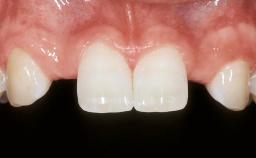

In February 2005, a 25-year-old female patient, a nonsmoker, was referred to our clinic due to tooth 11 presenting a chronic fistula following unsuccessful root-canal treatment and several attempts at endodontic surgery. The dental history revealed that more than ten years earlier, teeth 11 and 21 had been traumatized during a sports accident. Consequently, 11 had lost its vitality, and there were two moderate fractures of the mesioincisal borders of the two central incisors that had been restored with direct composite restorations. At the time of examination, the composite restorations showed signs of wear, some discoloration, and marginal infiltration. The patient also complained about a moderate discoloration of the clinical crown of the non-vital tooth 11. The patient was in good general health, and her medical history revealed no significant findings.